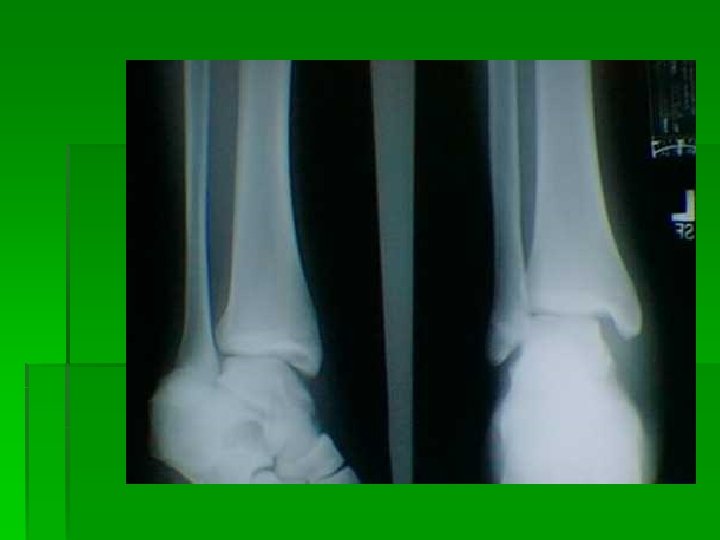

Distal Fibula fracture with associated medial deltoid ligament disruption. This injury is frequently the result of the foot being planted with a valgus load applied to the leg.

Notice the disruption of the medial deltoid ligament and the widening between the medial malleolus and the talus. This is indicative of a ruptured deltoid ligament.